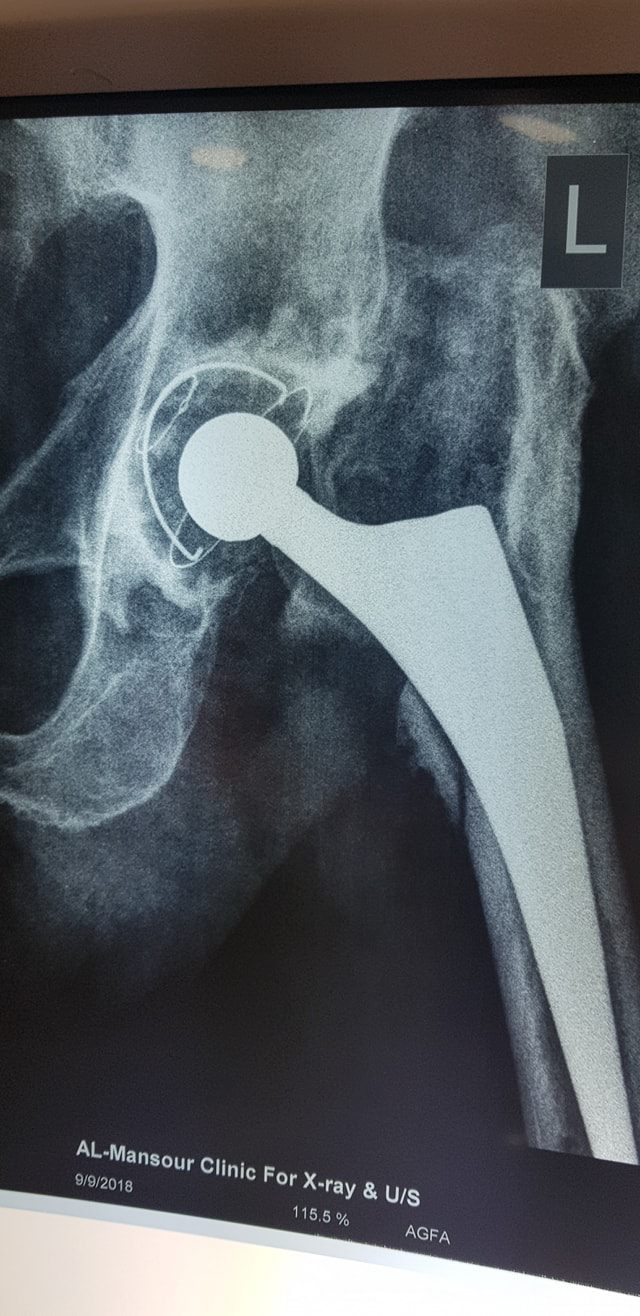

زراعة المفاصل الصناعية ورك و